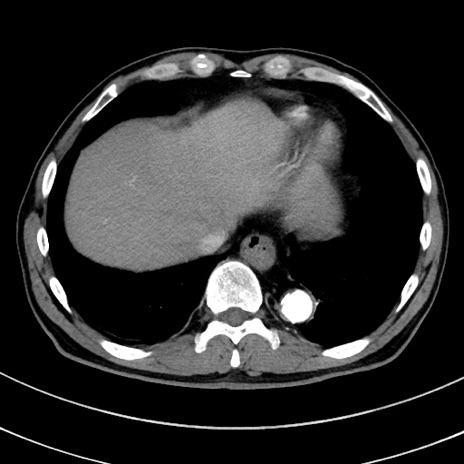

症例8(横断像)

【症例】 60歳代男性

【主訴】 黒色吐物

【現病歴】 4日前から嘔気自覚、2日前の朝食後にも嘔気あり、自分で手で嘔吐反射起こし嘔吐したところ血が混ざっていたため受診。

【既往歴】 5年前汎発性腹膜炎を伴う急性虫垂炎で手術、高血圧、前立腺肥大症、高脂血症

【身体所見】 腹部正中に手術癩痕あり 腹部平坦・軟圧痛なし膨満感あり

【データ】WBC 8400、CRP 4.54